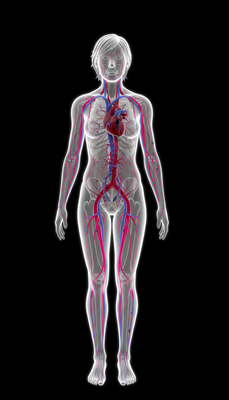

Cardiovascular Support

Unsaturated fatty acids (especially linoleic acid) may help lower cholesterol levels and reduce risk of heart disease.